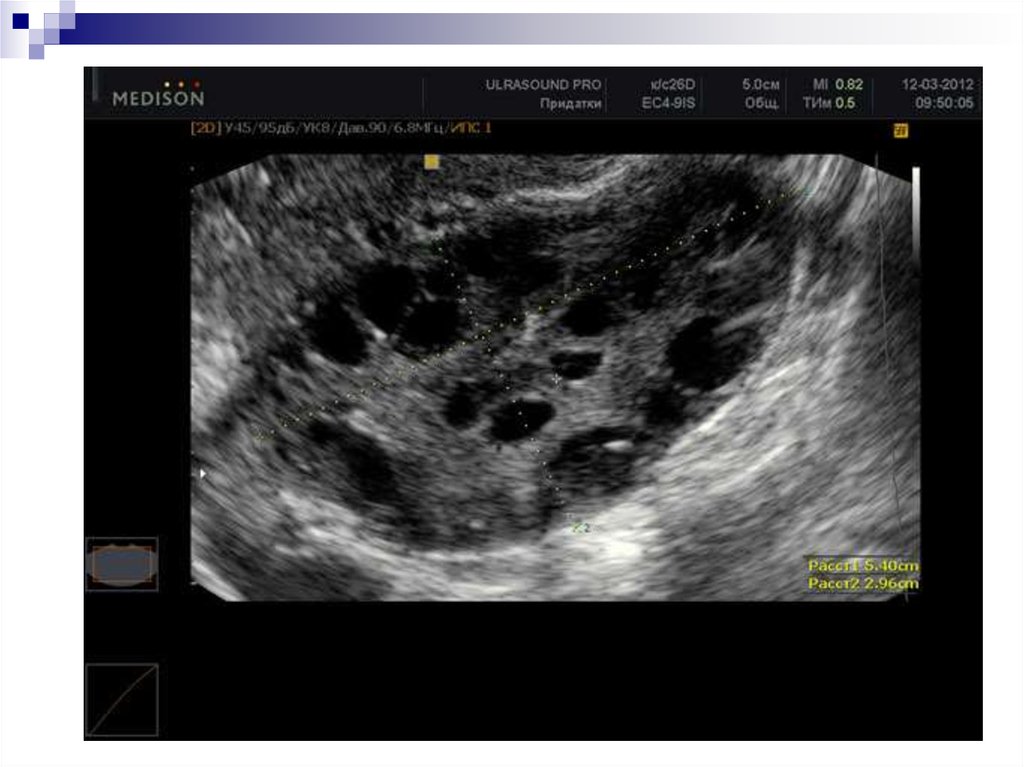

9. Инструментальные Исследования

Эхоскопические критерии поликистозных

яичников:

объём яичников более 8 см3;

увеличение площади гиперэхогенной стромы;

число анэхогенных фолликулов диаметром

до 10 мм не менее десяти;

усиленный кровоток и обильная сосудистая

сеть в строме (при доплерометрии).

3. Особенности морфологической структуры яичников

двустороннее увеличение размеров яичников

в 2–6 раз, гиперплазией стромы и текаклеток,

множество кистозноатрезирующихся

фолликулов диаметром 5–8 мм, утолщение

капсулы яичников.